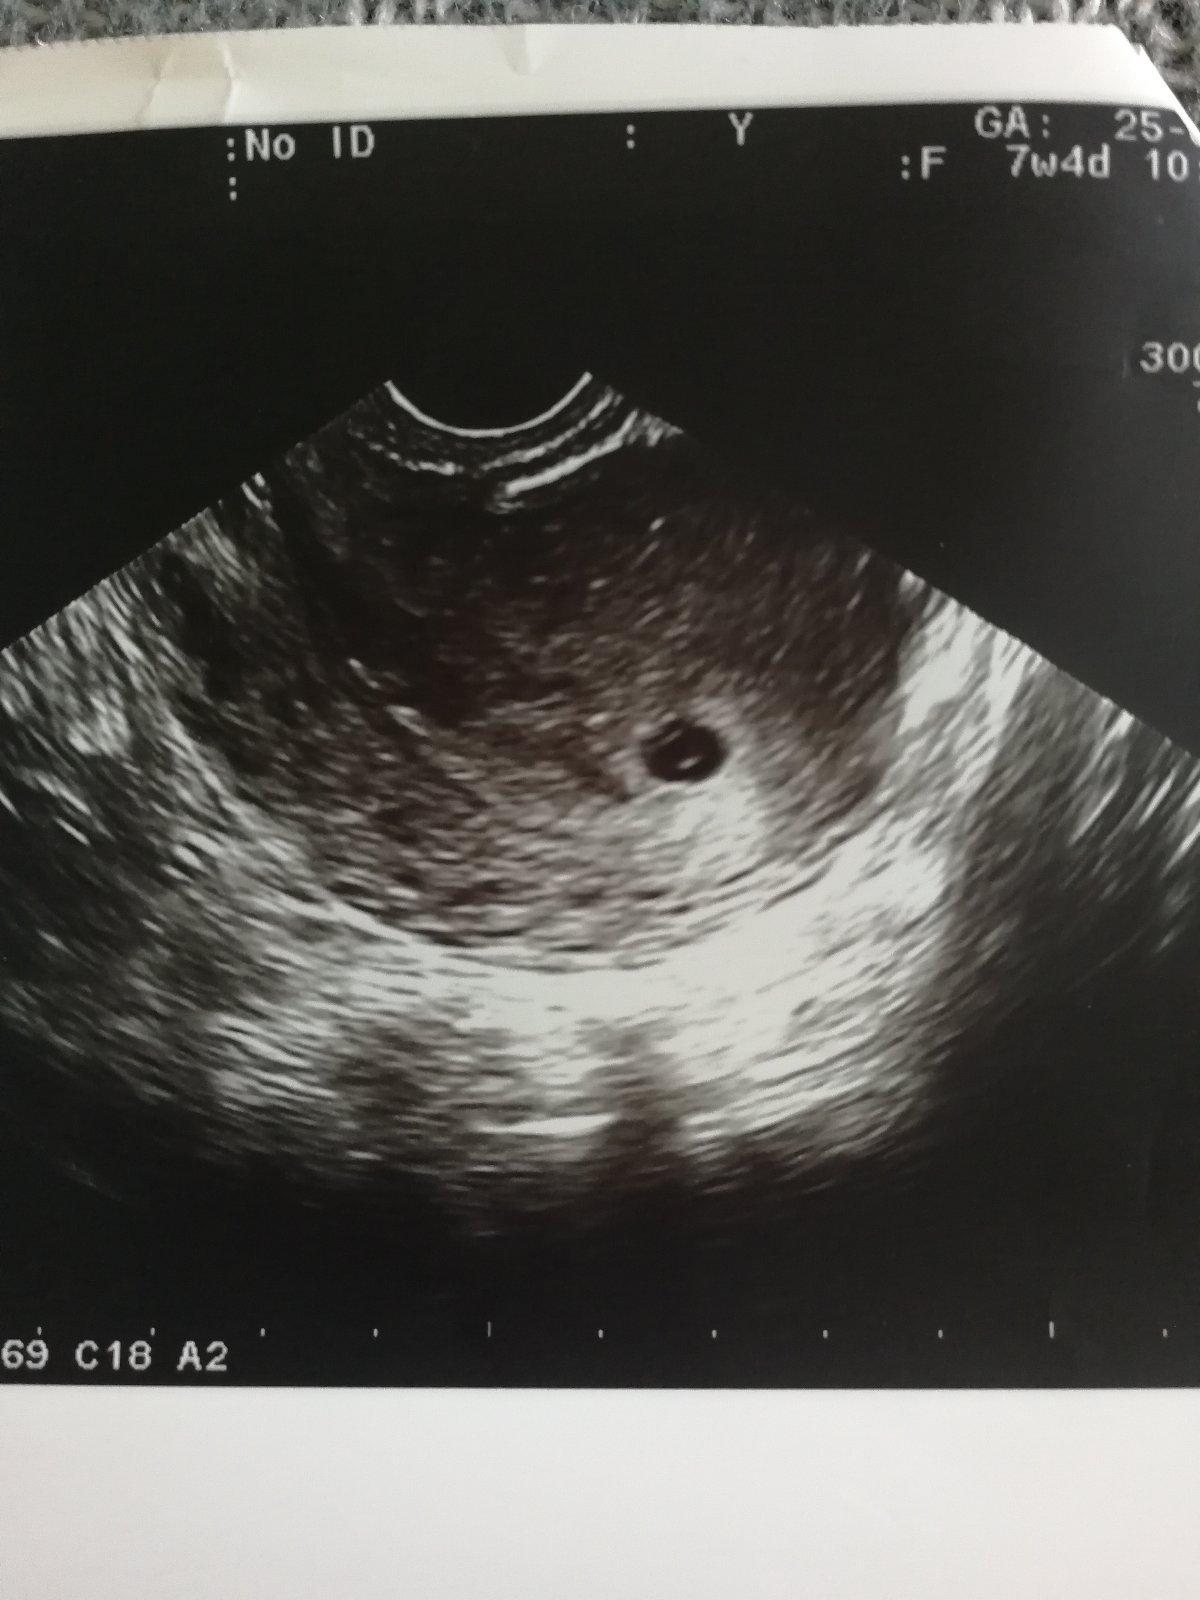

Progres ❤️

@08snazilka80 stvrtok vecer mam kontrolu ale tehotenstvo uz mam potvrdene aj z krvi aj zo sona 😊